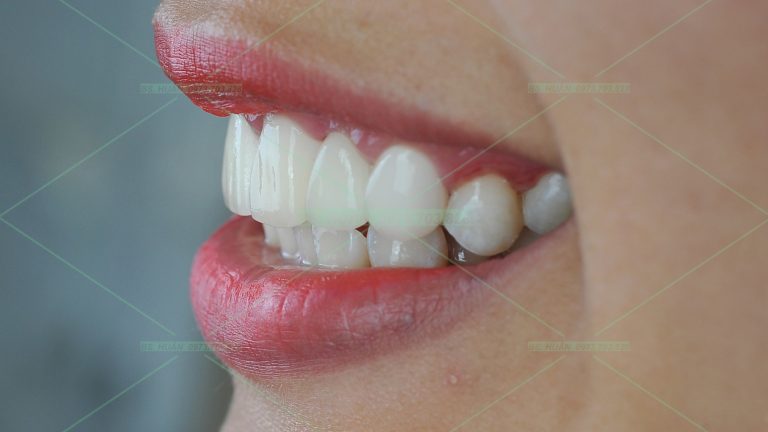

Răng sứ thẩm mỹ – N.T.L

Bạn nữ 29 tuổi làm chủ 1 nhãn hàng thời trang và thường xuyên phải thuyết trình giới thiệu sản phẩm, vì vậy ngoại hình rất quan trọng với bạn, nhất là nụ cười. Đây cũng là 1 ca được tư vấn chỉnh nha trước rồi làm răng sứ, cũng như những nguy cơ khi […]